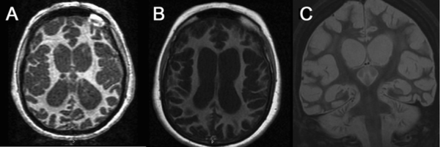

图2

MRI 1年之后

轴向fluid-attenuated反转恢复(A), t1 (B),日冕t2加权图像(C)揭示标志着旋转的萎缩和大脑皮层增厚CSF-like信号和侧脑室增大(pseudohypertrophic皮层)。同样明显的是弥漫白质高密度。